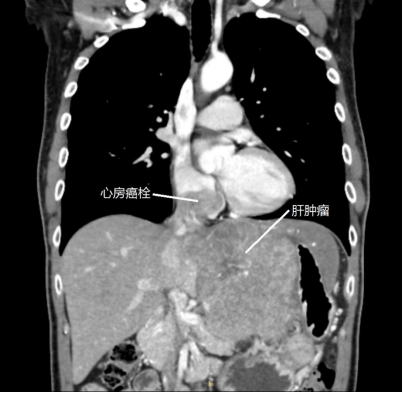

8月31日 , 陈先生转至中山大学孙逸仙纪念医院肝胆外科后 , CT检查提示:左肝癌巨块型肝癌 , 大小约13x13x12厘米 , 左肝静脉癌栓并突入右心房 , 癌栓大小约为4.5x4x3.8厘米 , 距三尖瓣1.5厘米 。 此外 , 右肺动脉主干及右下肺动脉干内充盈缺损 , 未完全堵塞 , 这表明肺动脉里已经开始出现栓子 , 但不确定是血栓还是癌栓 。

CT检查显示 , 陈先生肝脏肿瘤突入右心房